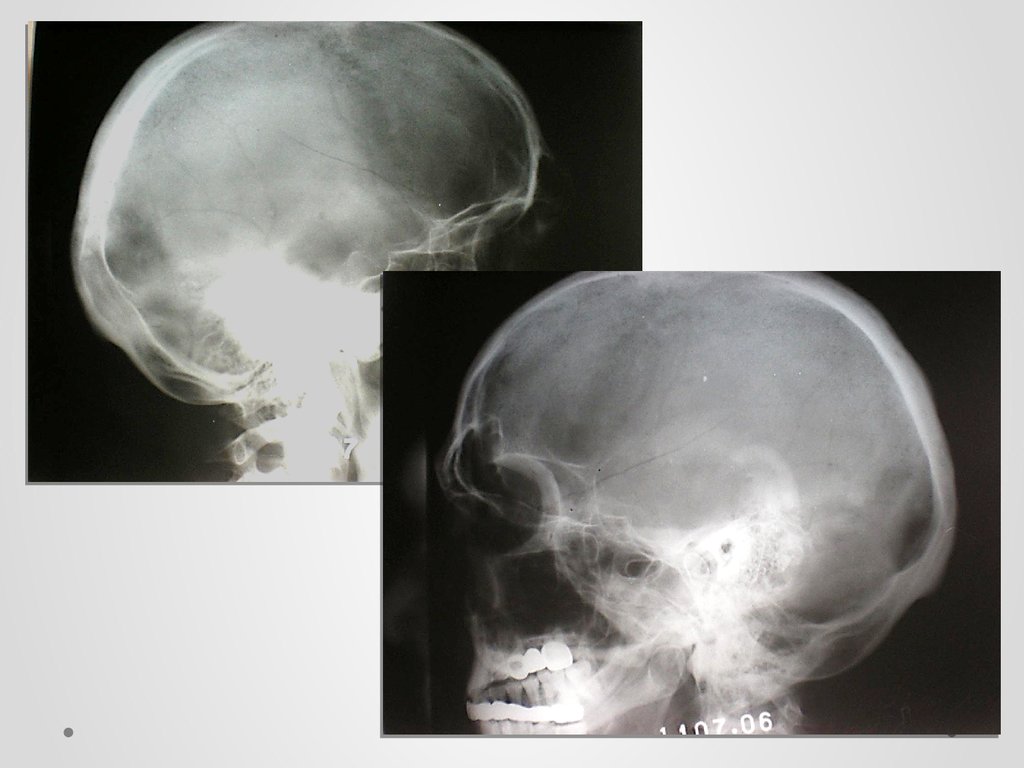

Рентгенография черепа и позвоночника: изображение и диагностика